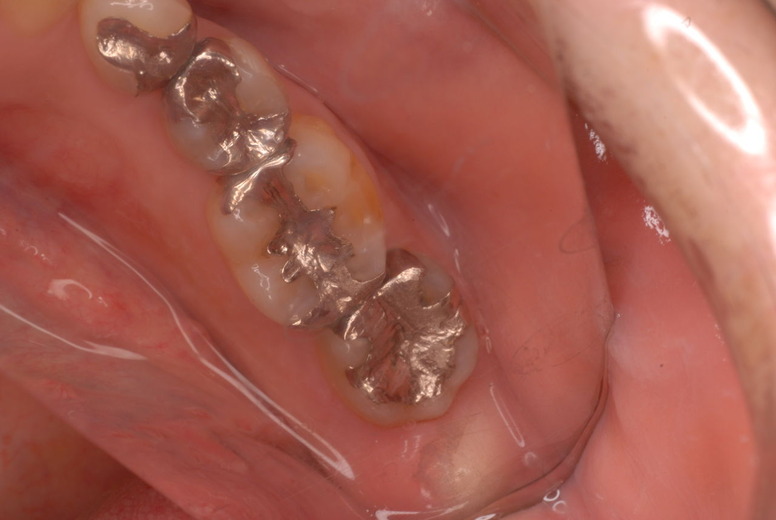

親知らずを取ることを嫌がる方が多いのですが、もし親知らずとその隣の14歳大臼歯の間に虫歯ができたり歯周病を罹患した場合、どれほど治療が大変で再発も起こりやすいか理解できない方がおおいのです。

写真左下の親知らずが痛くなり抜歯しました。その後歯茎を除去して虫歯を露出させる処置を二回ほどしています。

レントゲンでは小さいですが、こう言う虫歯が一番怖いのです。

治療の成功率は極めて悪くすぐ再発しやすいのです。